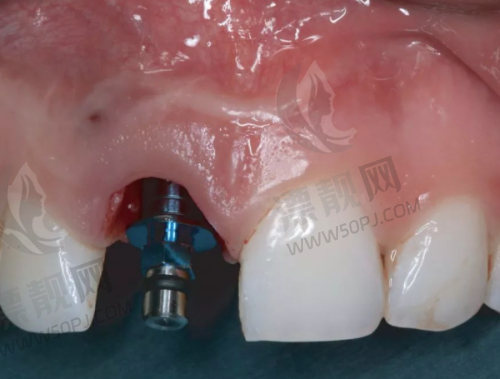

强项:高难度种植、全口修复、吸附性义齿

鼎植口腔在本地做种植牙的人中几乎是“必打卡单位”,医生高振华和黎强在种植牙领域经验颇为丰富,擅长全口吸附性义齿、即刻种植等复杂病例处理。此外,术前会有CBCT影像分析和3D导板定位,精细度特别高。价格一般,活动期间国产种植体可低至2980元/颗。